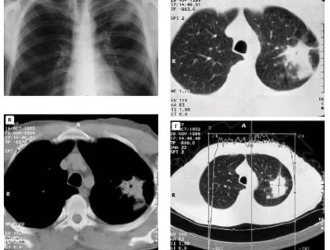

Диагностирование межрёберной невралгии

Первичная диагностика осуществляется на основе сбора анамнеза и жалоб пациента. В некоторых случаях этих данных достаточно для установления диагноза. Однако в сложных ситуациях может потребоваться дополнительное обследование, известное как дифференциальная диагностика, для исключения заболеваний с аналогичными симптомами.

Используются следующие методы:

- Рентгенография грудной клетки и позвоночника в различных проекциях для выявления межреберной невралгии.

- Магнитно-резонансная томография и компьютерная томография для исключения грыж и опухолей.

- Электрокардиография для проверки на наличие сердечно-сосудистых заболеваний.

Компьютерная томография даст более полное представление, если будет выполнена совместно с миелографией.

Поскольку межреберную невралгию легко перепутать с другими заболеваниями, необходимо проводить дифференциальную диагностику для исключения следующих патологий: